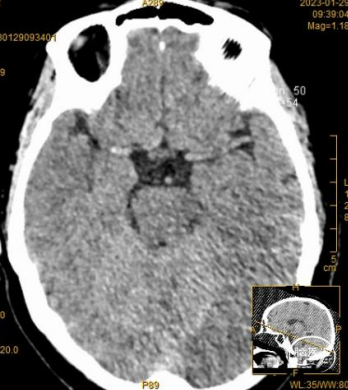

03 术前影像资料

溶栓前颅脑CT提示考虑右侧大脑中动脉致密征,支持大脑中动脉为责任病变。

溶栓后颅脑CT见右侧大脑中动脉远端致密征,右外侧裂池变窄,同并见“岛带征”,考虑右侧急性脑梗塞,必要时进一步MR检查和/或CT脑灌注成像。

术前MRA显示右侧大脑中动脉远端变窄并分支稀疏。